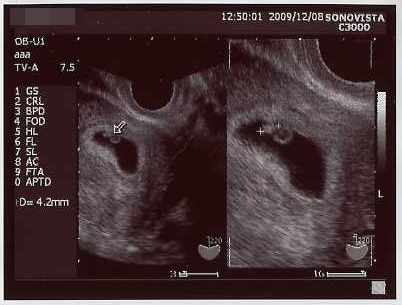

今日は検診でしたー

前回の倍の3.6センチに成長。

なんか劇的にでかくなった気がする!子宮の中いっぱいになってきたw

クリックで拡大。

今までのエコーも並べてみた →エコー写真

前回は、粘土の固まりにポコポコ手足をくっつけたみたいな形だったのが、

今回、首のくびれが出来、手足も伸びて、お人形さんみたいだった!

イヤーンて、寝返り打ちたいような感じで動いた姿が見れたのが嬉しかった。

こんなちっちゃい内から、胎動してるんだね~

心音も聞かせて貰った、今の心拍はオトナの倍位の速さだそうです(*´ω`)